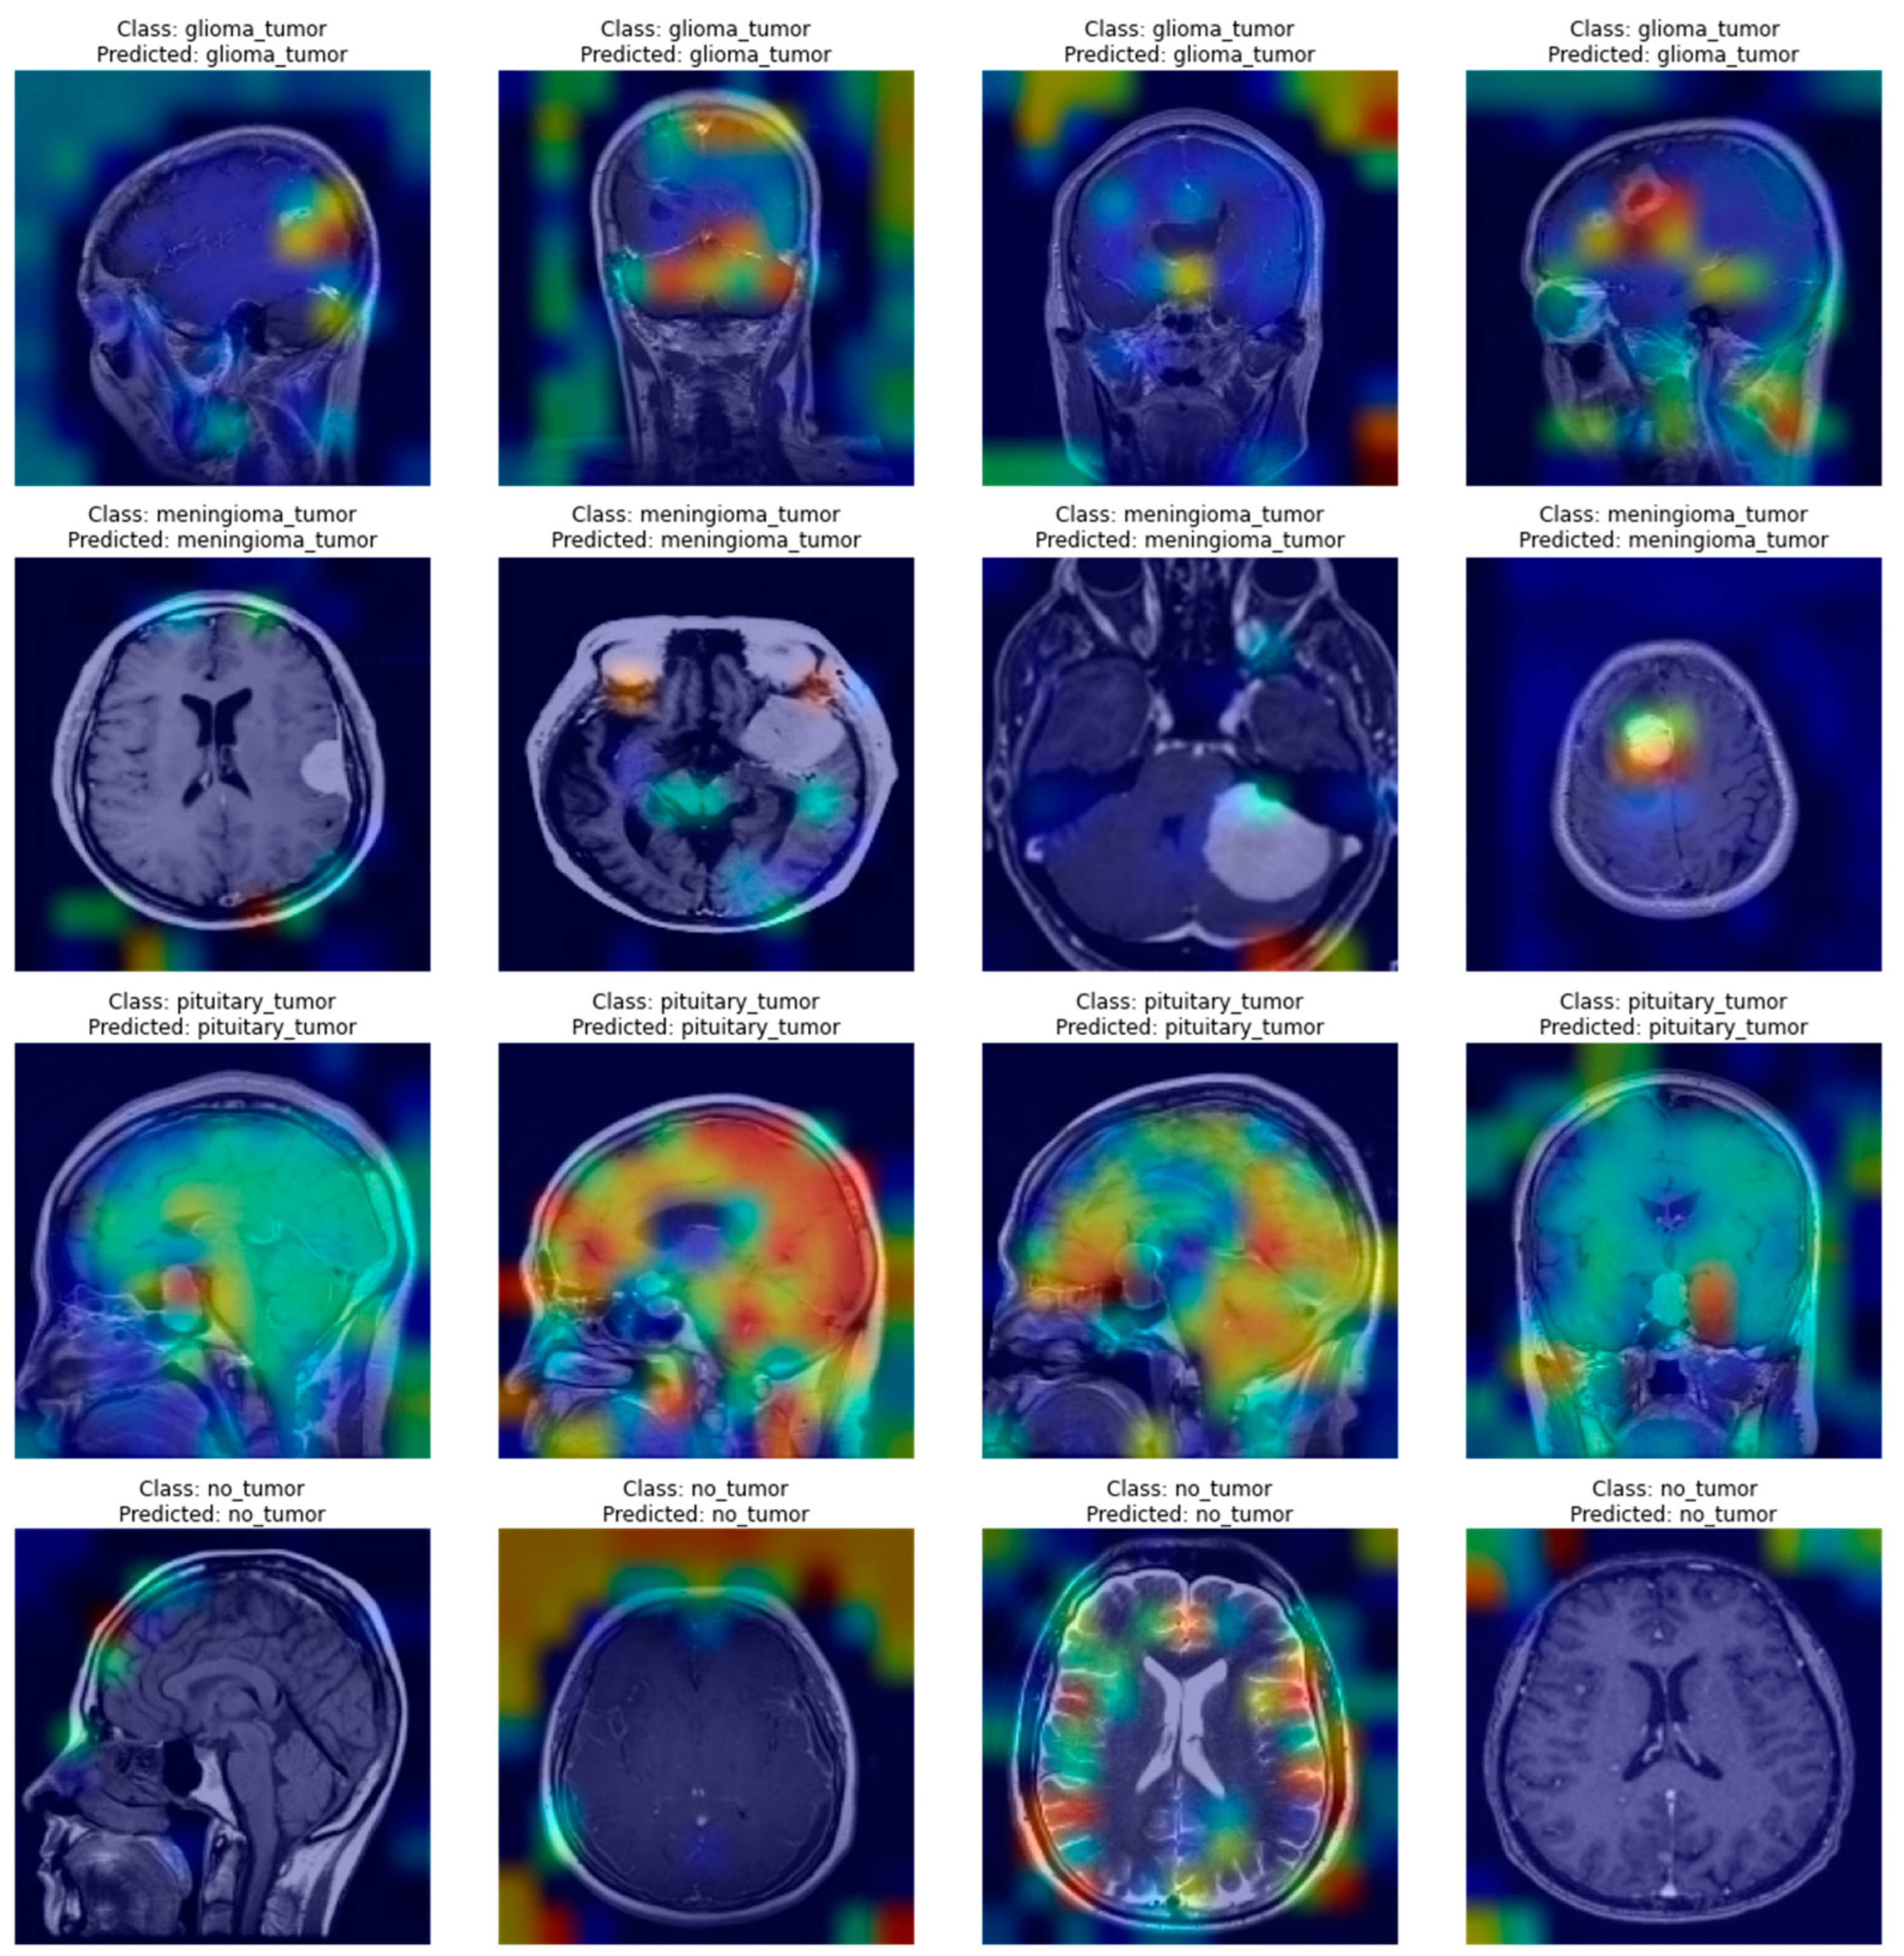

In the case of this research, explaining the decisions of neural networks is even more important than the raw scores the models achieved. It not only provides insights that allow us to assess whether the network truly learned how to solve the task but also emphasizes areas of the image important to the diagnosis. Figure 6 and Figure 7 present a few visualizations of classifications for simple versions of both types of architectures. The Grad-CAM for the CNN and Attention Rollout for the ViT were used to create the visualizations.

As can be seen in Figure 6 and Figure 7, both types of networks produced reasonable heatmaps, although in some cases, it is hard to say what made the network predict a specific class. Both architectures had problems marking up reasons for a pituitary tumor prediction, but in other cases, they were able to tag some interesting features, especially in the case of a meningioma tumor, with neoplastic changes clearly outlined from the background. Additionally, both methods do not mark anything specific in the case of no-tumor pictures, thus avoiding unnecessary noise that might distract the doctor examining scans.

The results of both algorithms are of comparable quality as they both mark similar features of the image. Still, one has to notice that the outputs of ViT’s visualizations are of better resolution, which is caused by the way the Attention Rollout casts the matrices weights by all the linearly scaling matrices of encoders, thus producing the outputs shaped similar to the network’s input. In contrast, the Grad-CAM produces a heatmap of the resolution of a chosen feature map’s dimensionality, which might differ between networks, and, in some cases, not provide satisfying outcomes. Such an example might be the Xception model, where the last convolutional layer produces feature maps of the 5 × 5 size, which does not provide any valuable insights. Furthermore, the ViT model’s visualizations show that it might be better in ignoring the background, which causes the output images to look less noisy.

It is noteworthy that these visualizations are only one of the many possible. There are different visualization algorithms, and they can be combined to achieve superior results. In addition, the output images shown in Figure 6 and Figure 7 are class-specific, which means that for every one of these images, a few more visualizations might be created, which would allow for checking whether anything was omitted while making a diagnosis.

Figure 6. A few examples of Grad-CAM produced heatmaps for the simple CNN’s decisions.

Applsci 12 11880 g006